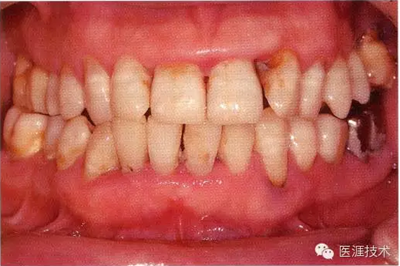

55歲牙周炎男性的臨床照片

55歲男性抽煙患者(1天20支、抽煙35年)。菌斑控制得不好。通過牙周探診,全頜有4~9mm的牙周袋,有1~3度的根分叉部病變。通過X光片觀察,上頜前牙中度牙槽骨吸收,其他地方有中度牙槽骨吸收。受吸煙影響,牙齦纖維性肥厚,呈紅黑色。牙齦幾乎沒有浮腫和發(fā)紅,所以這個病例是從外觀上無法預(yù)測病癥嚴(yán)重程度的病例。